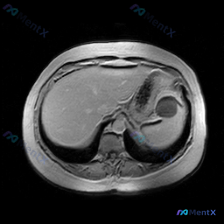

这是一张腹部MRI轴位T2加权图像,客观所见如下:

- 肝脏:信号大致均匀,包膜光滑,肝内胆管无扩张,未见明确高低信号结节;

- 脾脏:划重点——形态正常,信号强度均匀,未见明确局灶性高/低信号、占位或异常强化(当然本序列没有增强);

- 胃:腔内可见气-液平面(液体高信号,气体低信号),胃壁结构看起来还可以,没有明显增厚或肿块;

- 血管/腹膜后:腹主动脉、下腔静脉流空正常,腹膜后没有明显肿大淋巴结,也没有腹水或周围水肿。

脾脏轮廓清楚、包膜光整,T2像上实质信号均匀——既没有提示囊变/脓肿/水肿的局灶高信号,也没有提示纤维化/钙化/含铁血黄素沉积的局灶低信号,周围脂肪间隙也很干净。

👉 所以在这张图的层面内,没有支持「脾脏局灶性病变」的影像学证据。